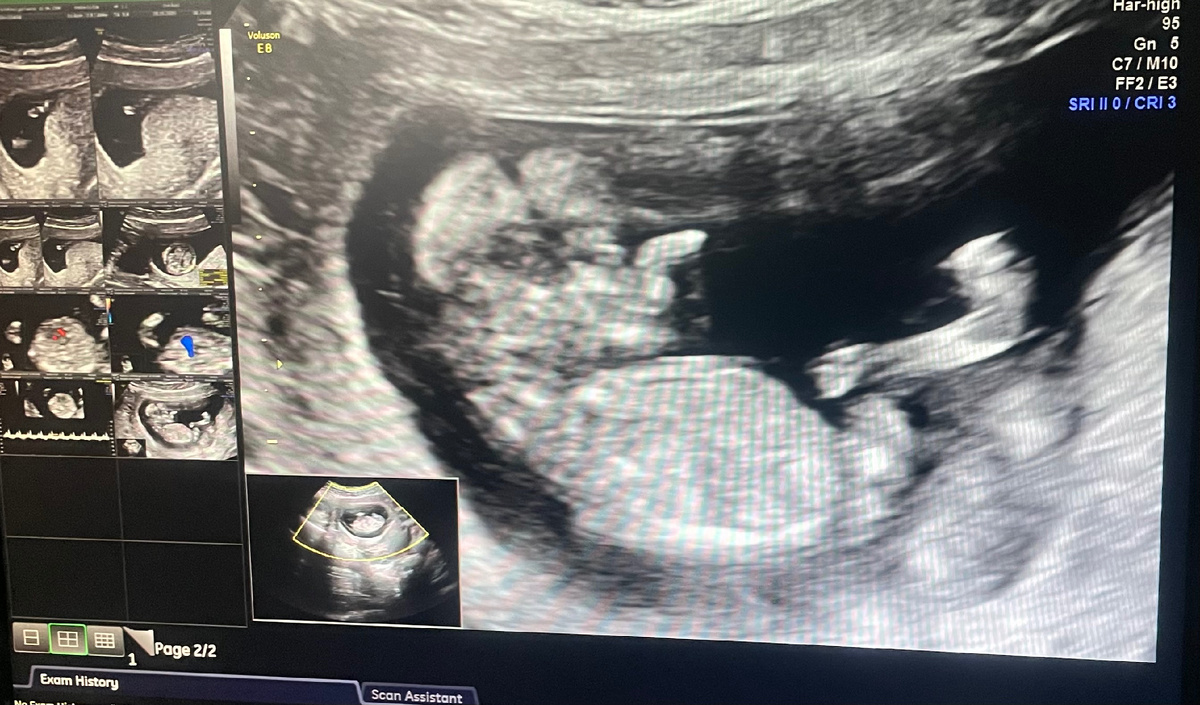

Врач никак не могла поймать изображение, чтобы ручки убрал от лица 🙂

Скрининг я проходила в КДЦ «Охрана здоровья матери и ребенка». Несколько кабинетов УЗИ, несколько гинекологов принимают. Народу много, но в очереди сидела минут 10~15. Сделали УЗИ, все показывают, объясняют по ходу исследования, но фотографию не делают, можно на телефон потом сфотографировать. После отправили в процедурный на сдачу крови, проверяют на хромосомные патологии. И в конце прием гинеколога. Через неделю звонит гинеколог, который принимал, и объясняет всё по анализу, дает дальнейшие рекомендации, следующий прием назначает. У меня всё в пределах нормы было, НИПТ проводить не требуется, чему я очень рада.